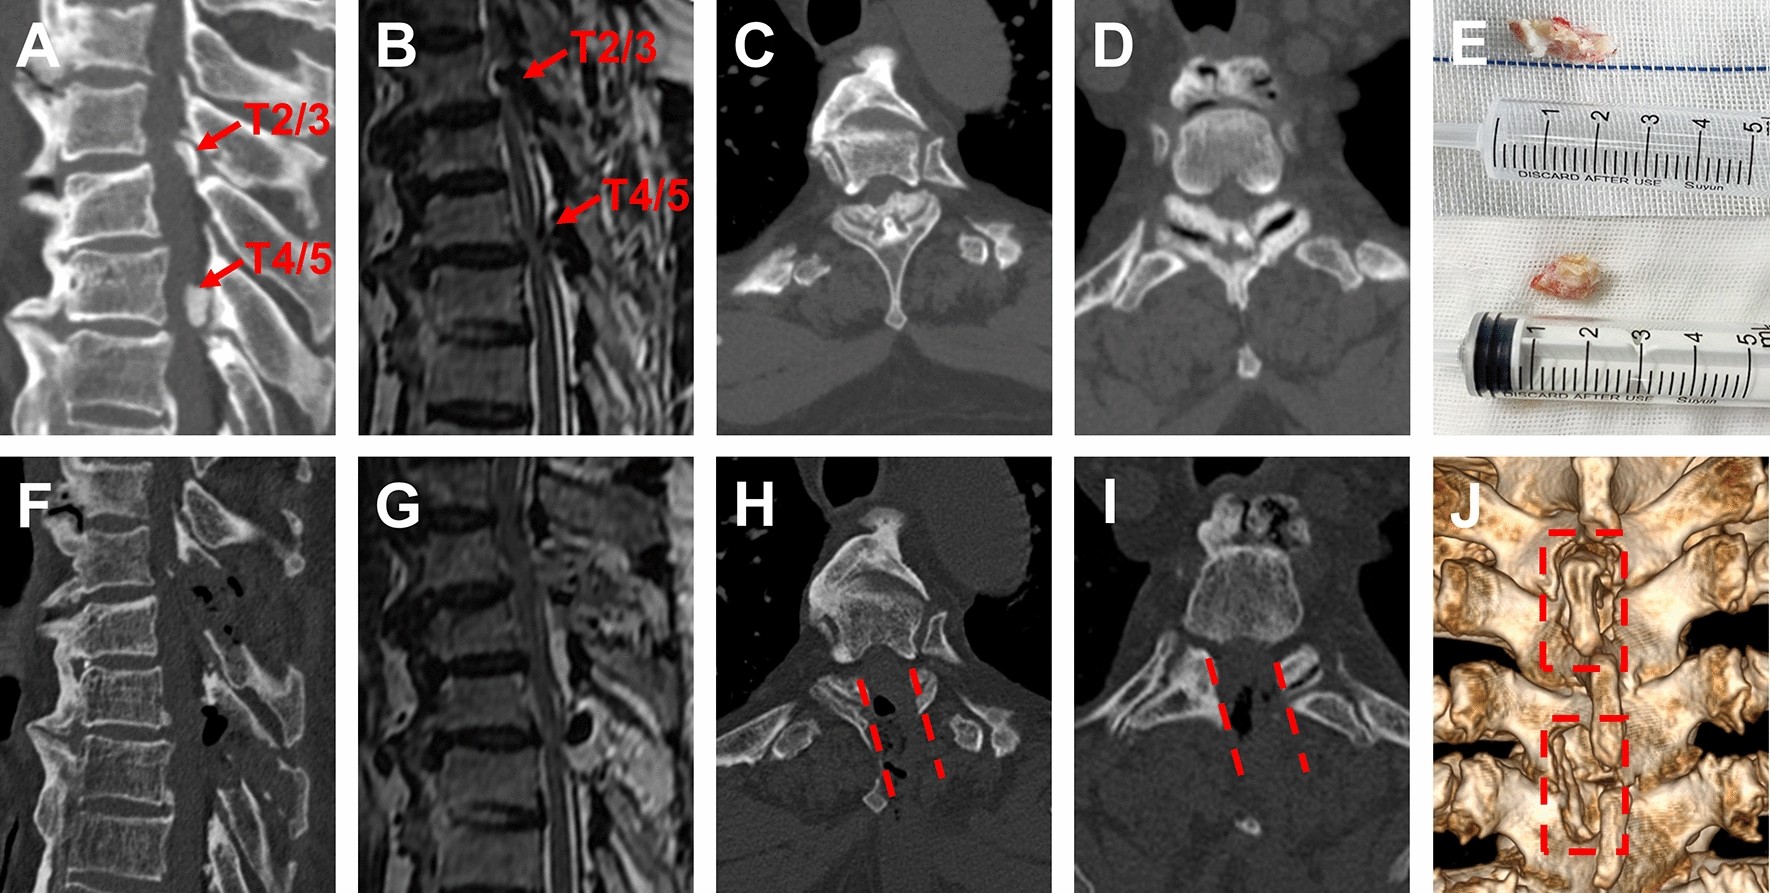

Figure 3

Two segments TOLF treated with OSE procedure. (A–D) Preoperative sagittal, axial CT and MRI images of TOLF, and the ossification lesion compressed the spinal cord at T2/3 and T4/5. Long T2 signal in spinal cord on MRI (As shown by the red arrow). (E) Remove the ossification lesions of T2/3 and T4/5 in piece. (F–I) Postoperative sagittal, axial CT and MRI images, demonstrated a complete remove of ossification lesion (As shown by the red dashed) and good decompression of spinal cord at T2/3 and T4/5. (J) Postoperative 3D-CT image showed the range of unilateral laminectomy at T2/3 and T4/5 (as shown in the red dashed region), bilateral decompression of spinal cord through unilateral approach.